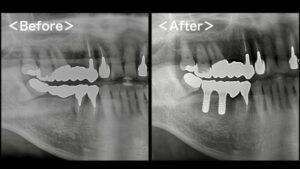

サイナスリフト

頬の骨の中は大きな空洞になっており、その部分を「サイナス(上顎洞)」といいます。サイナスを覆う粘膜を持ち上げて上顎の骨との間にすき間を作り、そこに骨の素になる物質を注入し、骨が作られるのを待ちます。